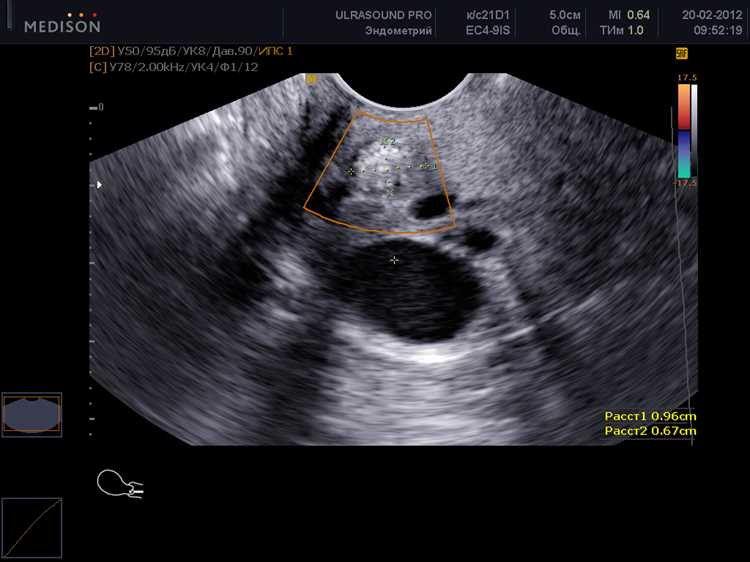

Что именно видно на УЗИ на 5-6 неделе?

На этом этапе также выявляется желточный мешок. Это образование дает питательные вещества развивающемуся организму до тех пор, пока не начнет функционировать плацента. Он может быть хорошо виден и служит важным индикатором здоровья.

Среди других находок – сердечная деятельность эмбриона. Сердце начинает биться примерно на шестой неделе, и на экране можно фиксировать его ритмичные сокращения. Это явление – ключевой показатель, подтверждающий развитие.

| Форма | Размер | Примечания |

|---|---|---|

| Эмбрион | 5-10 мм | Сердцебиение обычно заметно к 6 неделе |

| Желточный мешок | Около 1-2 см | Обеспечивает питание до формирования плаценты |

Важно отметить, что результаты могут варьироваться в зависимости от индивидуальных особенностей организма и качества используемого оборудования. В любом случае, профессионал сможет дать полную оценку развития на этом этапе.

Сердцебиение эмбриона можно определить примерно на 6-7 неделе гестации. В этот период размеры эмбриона достигают около 4-5 мм, что позволяет распознать биение сердца. На этом этапе оно может быть заметно не на всех аппаратах. Наиболее точные показатели можно получить при использовании современного оборудования.

На 6 неделе пульсация в сердце становится постоянно заметной, и её частота варьируется от 100 до 180 ударов в минуту. При этом, в зависимости от специфики индивидуального развития, существует возможность зафиксировать первые признаки сердцебиения чуть позже – на 8 неделе.

Для оптимального результата специалисты рекомендуют проводить первый осмотр на ультразвуковом сканировании в 7 недель, когда вероятность обнаружения пульсации значительно возрастает. Важно учесть, что некоторые факторы, такие как положение эмбриона или качество аппарата, могут повлиять на видимость сердечного ритма.